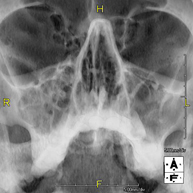

Técnica mediante la cual, utilizando rayos X, se obtienen imágenes del cráneo para su estudio. Indicaciones: traumatismo, cierre precoz de suturas craneales. - RX Senos Paranasales

Técnica mediante la cual, utilizando rayos X, se obtienen imágenes de los senos paranasales para su estudio. Indicaciones: dificultad respiratoria nasal, tos crónica, cefalea, mucosidad. - RX ATM (Articulación Temporo-Mandibular)

- Paranasal Sinuses X-ray

This technique uses X-ray rendered imaging for examining the paranasal sinuses. Indicated for: headache, chronic cough.